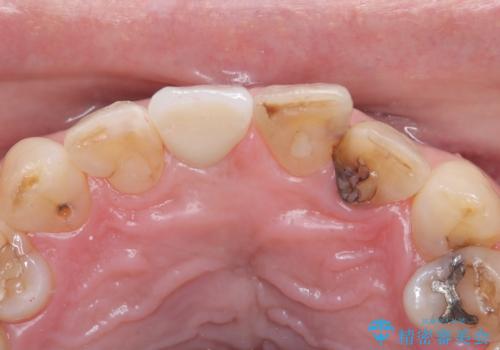

前歯は見た目の印象に大きく関わる部位であるため、できる限り治療期間中の審美性と機能性を損なわないことが求められます。患者さんとも相談のうえ、抜歯と同時にインプラント体を埋入する「即時埋入インプラント」を選択しました。これにより治療期間の短縮と、歯ぐきや骨の形態を保ちながらの審美的回復が可能となります。

治療は、まず感染の原因となっていた前歯を慎重に抜歯し、抜歯と同時にインプラントを埋入しました。審美性を重視する部位であるため、骨や歯ぐきのボリュームを維持するための補填処置も併用しています。術後は仮歯を装着し、見た目を保ちながらインプラントと骨がしっかりと結合するのを待ちました。

約3か月の治癒期間を経て、最終的にセラミックの上部構造を装着。周囲の歯や歯ぐきとの調和を図りながら、自然な見た目としっかりとした噛み心地を再現しました。患者さんからは「折れて落ち込んでいたが、見た目も噛み心地も元通りで嬉しい」とのお声をいただきました。即時埋入により、精神的な負担も少なく治療を終えることができました。